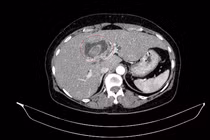

Vàng da người phụ nữ đi khám, phát hiện ca bệnh hiếm, hai ung thư nguyên phát

Việc phát hiện đồng thời hai ung thư nguyên phát trong hệ tiêu hóa là rất hiếm. Trường hợp này cho thấy vai trò quan trọng của thăm khám toàn diện.